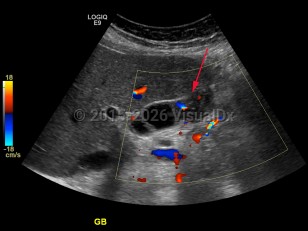

Gallbladder carcinoma

Patients may be asymptomatic at the time of presentation or demonstrate nonspecific findings, including right upper quadrant pain. They may have typical symptoms of cholelithiasis in early disease or with advanced disease, and may present with anorexia, weight loss, and vomiting. Ninety percent of gallbladder neoplasms are adenocarcinoma with the remainder adenosquamous, squamous cell carcinoma, small cell neuroendocrine tumors, lymphoma, and sarcoma. Papillary carcinomas have the most favorable prognosis while adenocarcinomas may extend outside of the gallbladder and invade the liver as they grow. Prognosis is dependent on histologic type and the extent of invasive carcinomatous disease.